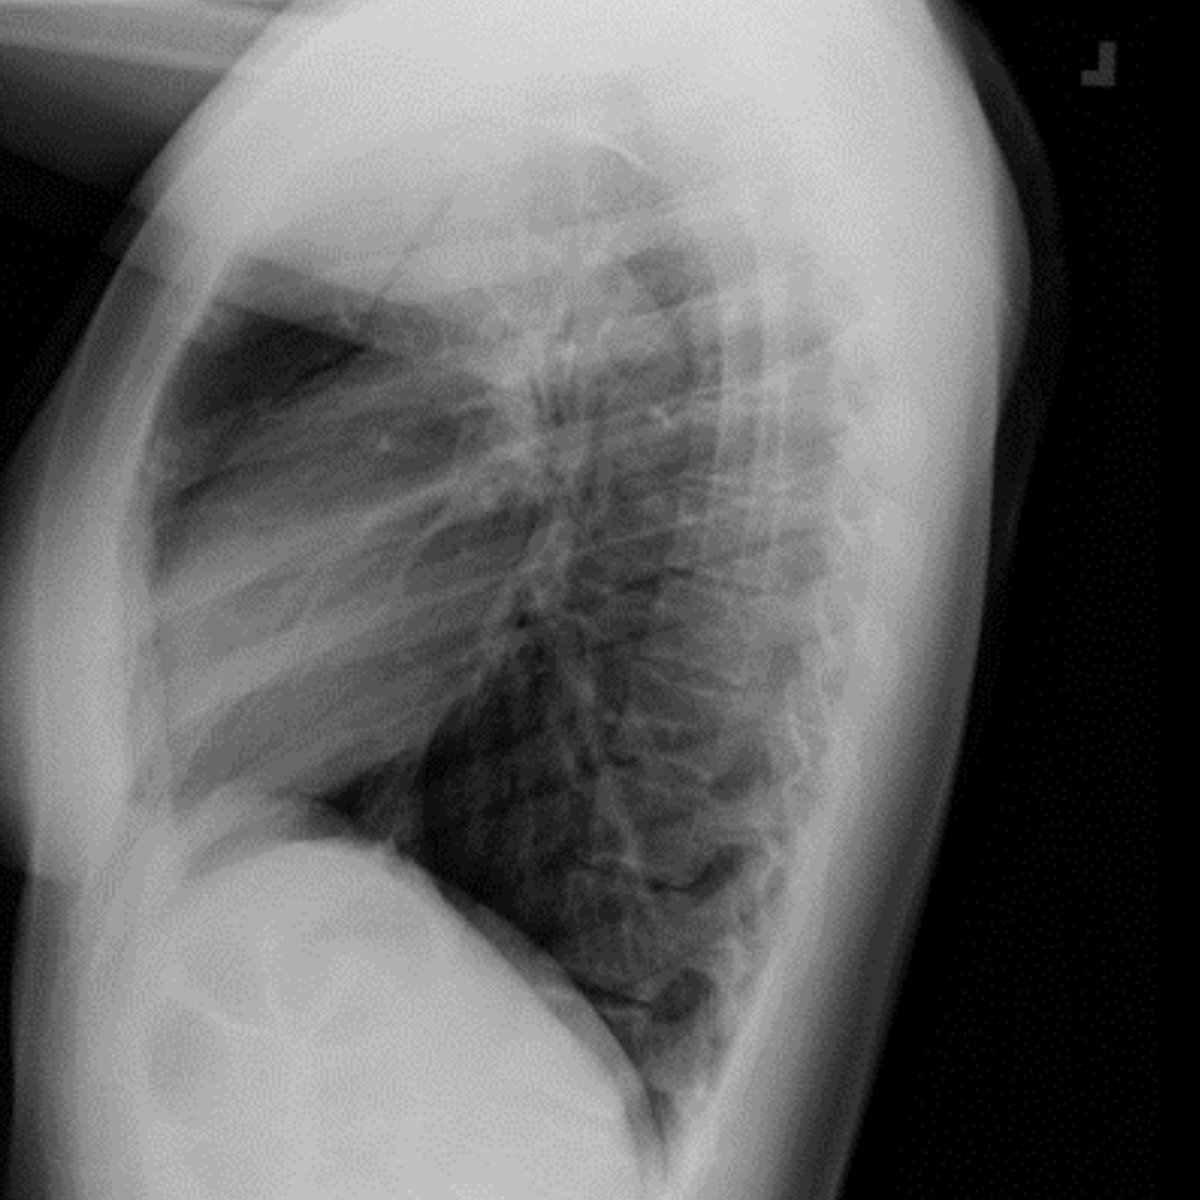

Have you seen our November 2022 Thoracic Case of the Month? 77 yo F w/ 40-year smoking history, presents with worsening shortness of breath and left rib pain… submitted by @AWSongMD & Joseph Lowry MD from Staten Island University Hospital. thoracicrad.org/assets/index/2…